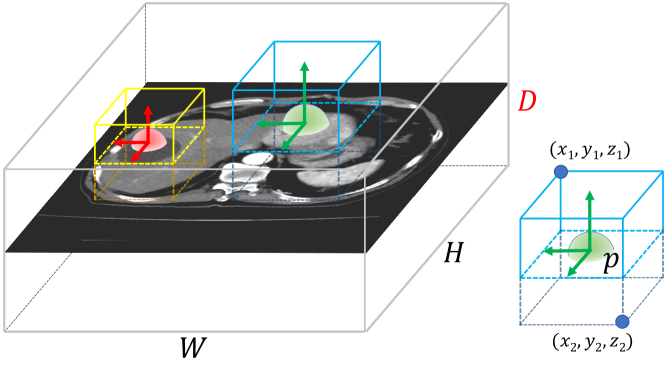

As depicted in Fig. 3, we opt for a 3D extension of 2D CenterNet detector [21]. The one-stage and anchor-free CenterNet based object detection models offers both high performance and simplicity, and does not require tuning anchor-based hyper-parameters required by two-stage and anchor-based approaches. We choose 3D detection because the the intrinsic 3D structure of tumors may be too visually ambiguous when only observed from 2D slices [28]. CenterNet [21] follows a \acFCN pipeline and the primary outcome is a 3D heatmap, , where is the downsampling factor of the prediction map. The heatmap should equal to at lesion centers and otherwise. We extend the stacked Hourglass-104 network [50] in the original CenterNet formulation [21] to a 3D variant. Following CornerNet [31] and CenterNet[21], the ground truth of 3D target center points can be modeled as a 3D Gaussian kernel. Nevertheless since volumetric medical images are often non-isotropic, (i.e.,, the physical voxel spacing in , e.g., 5 , is larger than that in and , e.g., 1 ), we use instead a non-isotropic Gaussian kernel:

| (1) |

where , , and are the downsampled target center points and is the kernel standard deviation. , , and are the resolution coefficients to compensate for resolution differences. The corresponding pixel regression loss , and the -norm offset prediction loss , are formulated identically as Zhou et al. [21].

Given any 3D bounding box , the center point is modeled as . The true bounding box size is computed as . For a predicted bounding box , the size loss at the center point is calculated:

| (2) |

For generality, we employed the same hyper-parameter settings as [21] to combine the three loss functions (, , ) and to set . To fit CT volumes into GPU memory, we first apply a robust multi-phase liver segmentation model [raju2020coheterogeneous], crop around the resulting mask, and then resample the CT subvolume into 17625648.